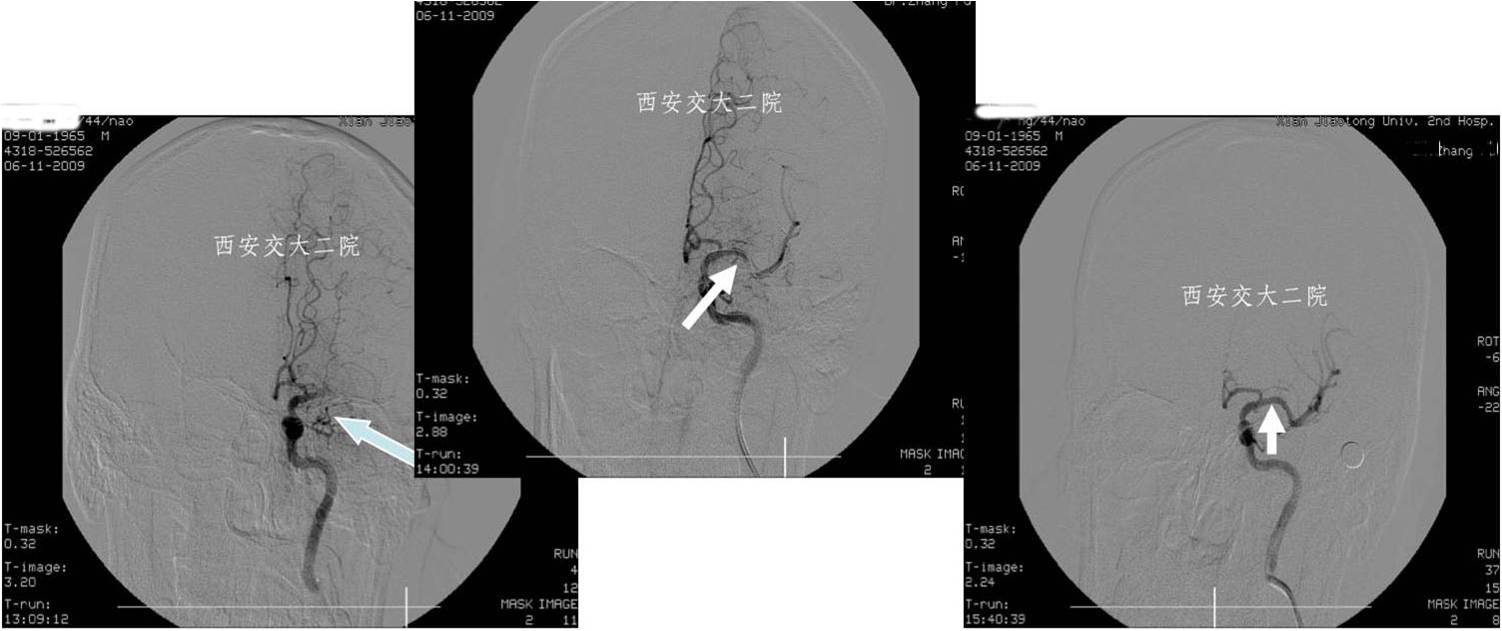

Case 2 左侧大脑中动脉溶栓+支架 (2009年)

》男,44岁,突发言语不能,右侧肢体活动不灵2小时。

》尿激酶10万后MCA未通,给予Apollo支架植入。

术后即刻CT

术后5天脑CT